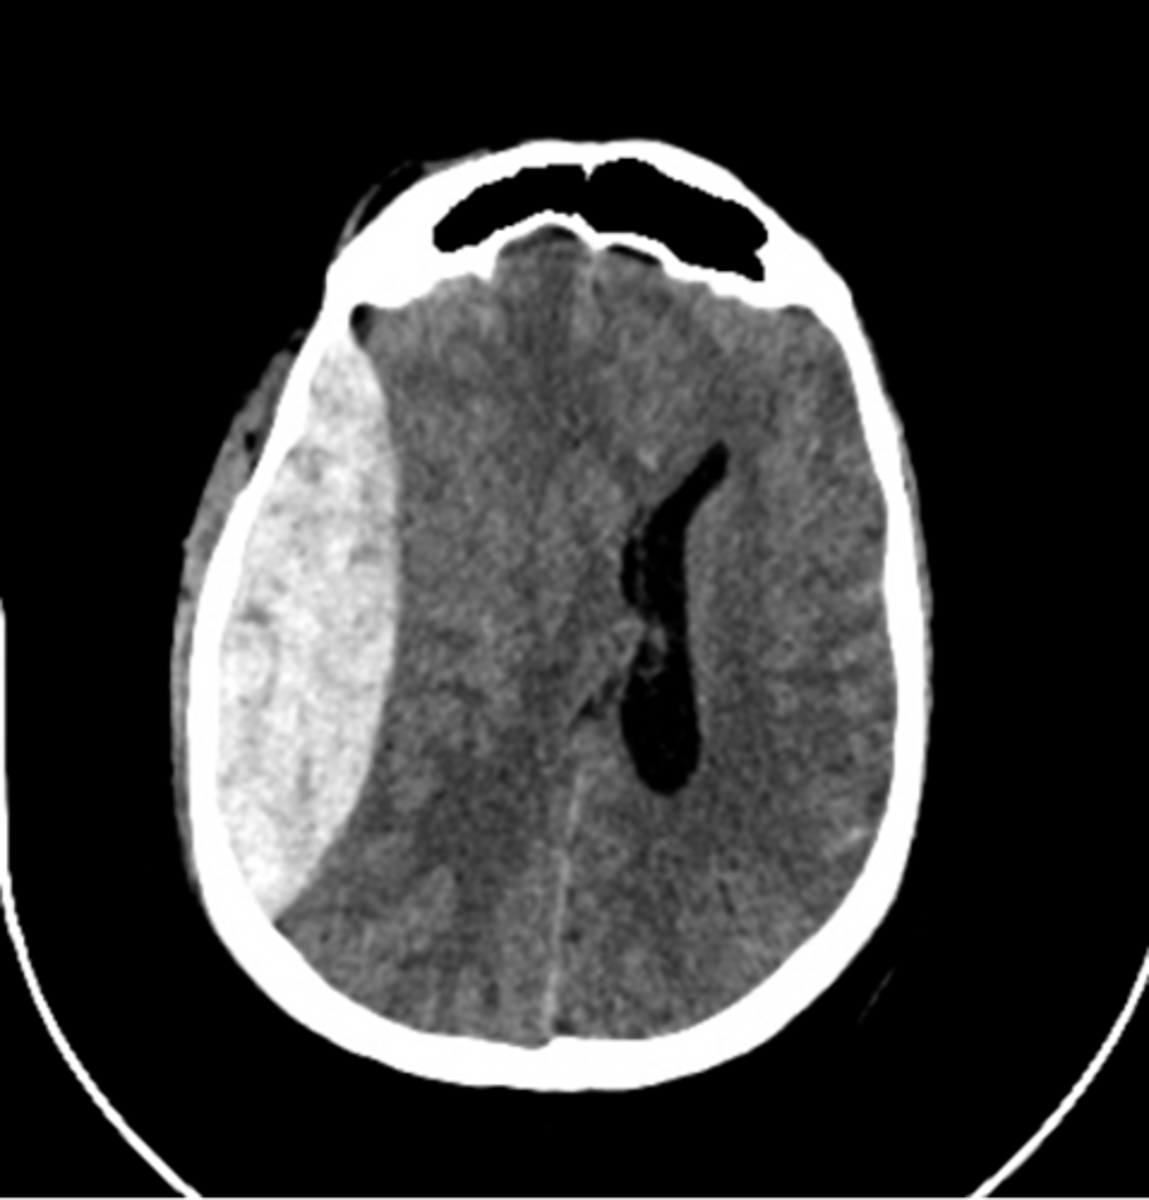

epidural hematoma

lemon shaped

normal mental status to completely unconscious

subdural hematoma

Crescent-shaped intracranial bleeding after head injury in the elderly; can be acute on chronic

Dark (on CT) means

old blood

White means

new blood or CSF

Can you have a subdural hematoma that is acute on chronic?

yes